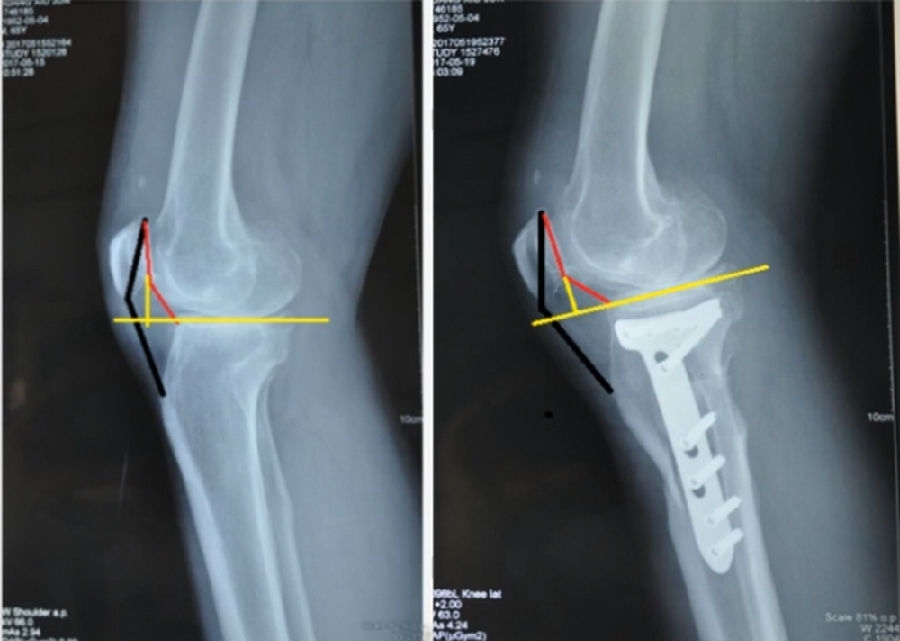

典型病例,女性,56岁,农民右膝内翻18度。

术前影像

术中影像

结合影像学来看,该患者单纯用闭合截骨或开放截骨,对肢体均有影响,所以决定采用混合型截骨。术中混合截骨旋转中心选在内外1/3处,先做闭合楔,然后顺势将开放楔敲开,达到术前设计的目标力线。术后随访力线达到要求。

术后X线